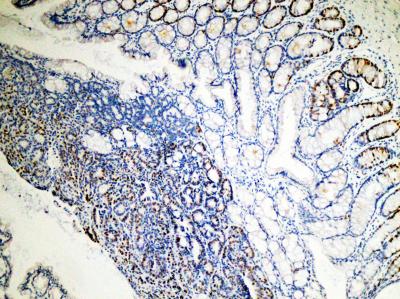

"We found an interesting correlation in colon cancers—if a patient's tumor doesn't produce PKCζ, he has a poorer prognosis than a similar patient with the protein. We looked specifically at colon cancer in this study, but it's likely also true for other tumor types," said Jorge Moscat, Ph.D., a professor in Sanford-Burnham's National Cancer Institute-designated Cancer Center. Moscat led the study in close collaboration with Sanford-Burnham colleague Maria Diaz-Meco, Ph.D.

Although most cancer cells love glucose, tumors lacking PKCζ grow even better in the absence of this nutrient. Using human tumor samples and a mouse model of colon cancer, Moscat and his team determined this growth-without-glucose paradox is because PKCζ-deficient tumors are able to reprogram their metabolism to use glutamine, another nutrient, instead.